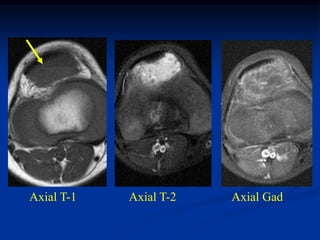

Case #273       Axial T-1 MRI

11 year male

lipoma

deltoid muscle

Coronal T-1 MRI